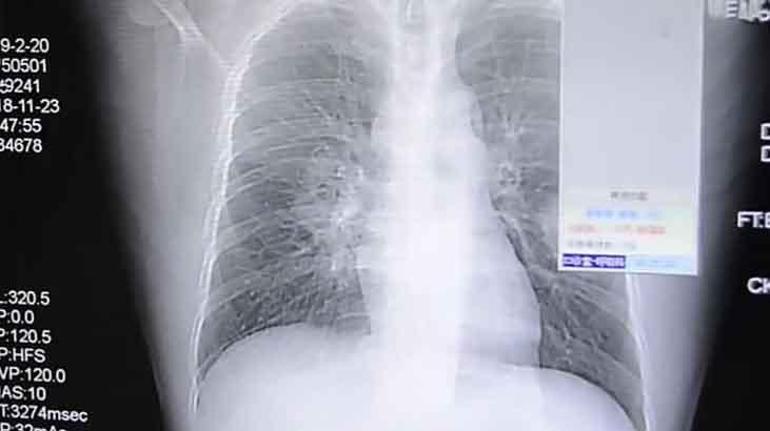

Ancak kelam konusu bu durum Çin’de yaşanan birinci hadise değildi. 2018 yılında ülkenin güneydoğusundaki Zhangzhou kentinde yaşayan 37 yaşındaki bir adam da öksürük ve göğüs ağrısı şikayetiyle hastaneye kaldırıldı. Hasta, sıhhat görevlileriyle yaptığı görüşmede, ‘giydiği çorapların kokusuna bağımlı hale geldiğini’ söyledi. Onun da ayakkabılarında gelişen sporlardan kaynaklanan mantar akciğerinde enfeksiyona yol açmıştı.

Çin’in Çongçing kentinde yaşayan adam (sağdaki resimde) şiddetli bir öksürük krizi geçirdikten sonra hastaneye kaldırıldı.